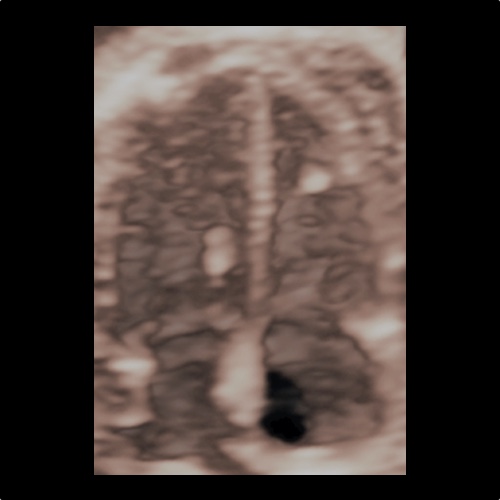

Ecocardiografia fetale